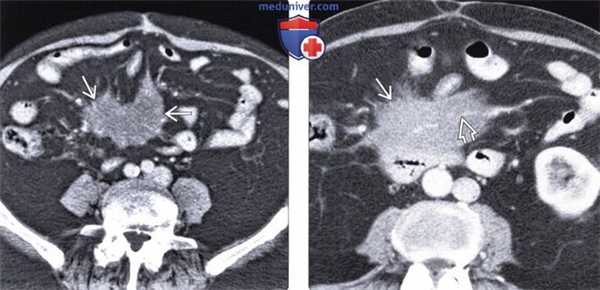

(Слева) На аксиальной КТ у пациента с болевой симптоматикой и лихорадкой определяется инфильтрация брыжейки тощей кишки, отграниченная псевдокапсулой. Визуализируются также множественные хорошо заметные брыжеечные лимфатические узлы с жировым «гало». При ПЭТ не было выявлено гиперфиксации радиофармпрепарата, симптомы регрессировали после назначения стероидной терапии.

(Справа) При аксиальной нативной КТ у пациента с длительно существующим болевым синдромом выявлена инфильтрация брыжейки тощей кишки с псевдокапсулой. Брыжеечные сосуды сдавлены, но без признаков обструкции. Все эти изменения являются проявлением и склерозирующего мезентерита.